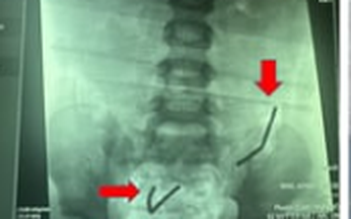

Một bé gái 6 tuổi ở Quảng Ngãi nuốt kẹp tóc bằng kim loại trong lúc ngủ trưa, bác sĩ đã nội soi gắp dị vật ra khỏi ổ bụng.

TP.HCM: Nuốt 20 viên nam châm, ruột non bé trai bị thủng 8 lỗ

Hy hữu: Nắp chai nằm trong bụng cụ ông 60 năm

Nam sinh nhập viện cấp cứu do nhét dị vật dài 60 cm vào niệu đạo

Người phụ nữ bị xương cá rô xuyên thủng thực quản và động mạch chủ ngực

Mắc dị vật đường tiêu hóa